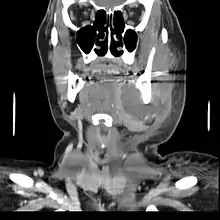

Internal drainage is of more concern as growing infection makes space within the tissues surrounding the infection. Severe complications requiring immediate hospitalization include Ludwig's angina, which is a combination of growing infection and cellulitis which closes the airway space causing suffocation in extreme cases. Also infection can spread down the tissue spaces to the mediastinum which has significant consequences on the vital organs such as the heart. Another complication, usually from upper teeth, is a risk of sepsis traveling through pathways to which it can possibly lead to endocarditis, brain abscess (extremely rare), or meningitis (also rare).